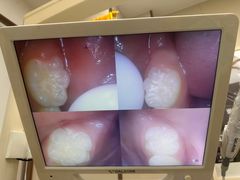

• 品凯口腔(丰潭门诊)

• -品凯口腔(丰潭门诊)